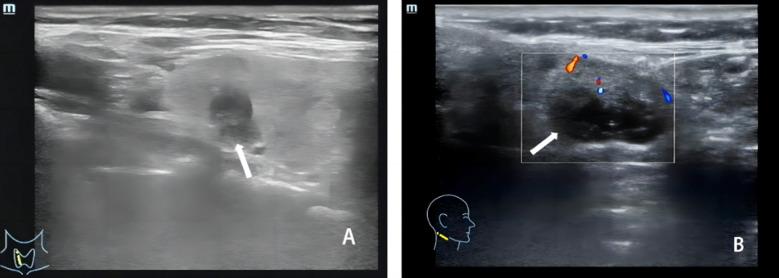

甲状腺乳头状癌超声检查参数与病理特征的相关性

The correlation between the ultrasound examination parameters and the pathological characteristics of papillary thyroid carcinomas.

To evaluate the correlation between ultrasound (US) examination parameters and pathological characteristics of papillary thyroid carcinomas (PTC).

METHODS

A retrospective analysis was conducted using clinical data from 89 patients with PTC (malignant group) and 89 patients with benign thyroid nodules (benign group) who underwent US at Chengdu Shuangliu Hospital of Traditional Chinese Medicine between February 2021 to February 2023. The correlation between ultrasound parameters and pathological features of PTC was analyzed.

RESULTS

Ultrasound parameters in the malignant group were significantly different from those in the benign group (<0.05). Peak systolic blood flow velocity (PSV), pulsation index (PI), and resistance index (RI) were significantly higher in patients with malignant lymph node metastasis (LNM) and stage III-IV PTC. In contrast, peak intensity (Peak), mean transit time (MTT), time to peak (TTP), and area under curve (AUC) were significantly lower than those in patients without LNM and stage I-II (<0.05). Spearman's analysis revealed significant correlations between ultrasound parameters, LNM, disease staging, and gene mutations (). Of the 89 PTC patients, 27 had disease recurrence, and five died during the follow-up. The poor prognosis group had significantly higher PSV, PI, and RI and lower Peak, MTT, TTP, and AUC compared to the good prognosis group (<0.05).

CONCLUSIONS

Ultrasound is a valuable tool for diagnosing and evaluating papillary thyroid carcinoma (PTC). It shows strong correlations between ultrasound parameters and pathological features, including lymph node metastasis and disease staging, aiding early diagnosis and prognosis prediction.